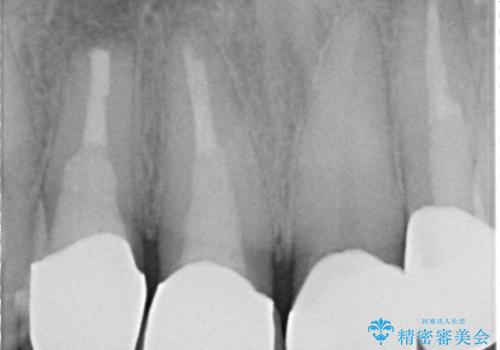

- 右上の前歯が土台ごと外れたといらっしゃった方の症例です。

ファイバーコアという土台から建て直し、咬み合わせに十分注意した上で、オールセラミッククラウンによる補綴を行いました

- オールセラミッククラウン…¥100,000、仮歯…¥10,000、ファイバーコア…¥20,000費用は治療当時の料金となります